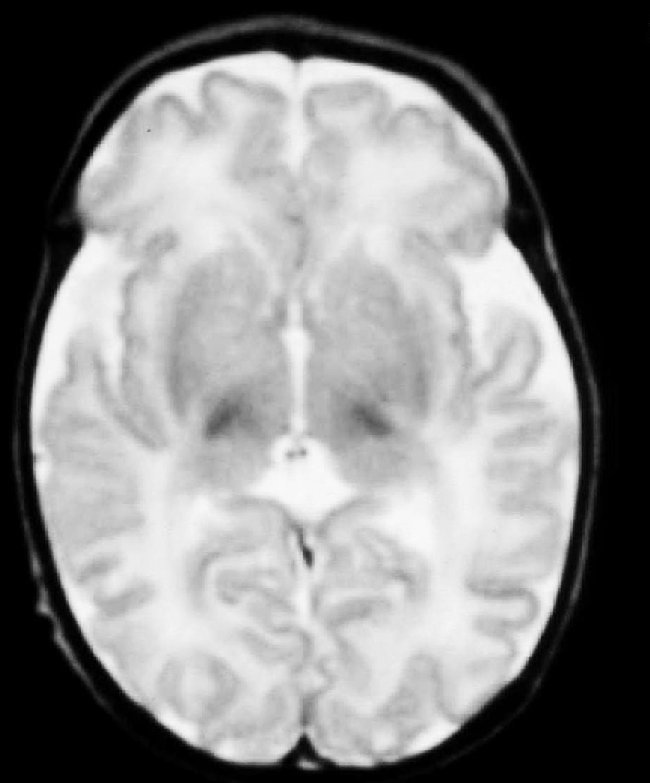

Fig. 3. Resonancia magnética.Secuencia T2 turbo en plano axial. Tenue hiperseñal al nivel de núcleos palidales de forma bilateral.

A las 48 horas de su ingreso presenta una crisis de hipertonía, motivo por el que se realiza una resonancia magnética.